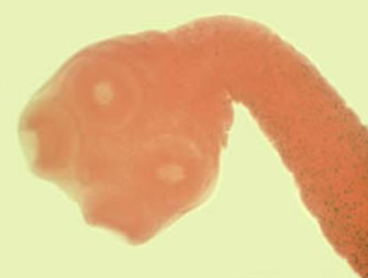

43

New cards

Ancylostoma duodenale (Old world hookworm) mouth

knowt flashcard image